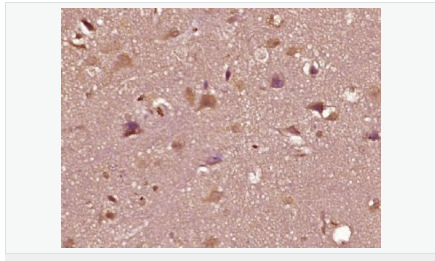

| 產(chǎn)品應(yīng)用 | WB=1:500-2000 ELISA=1:5000-10000 IHC-P=1:100-500 IHC-F=1:100-500 Flow-Cyt=1ug/Test IF=1:100-500 (石蠟切片需做抗原修復(fù)) not yet tested in other applications. optimal dilutions/concentrations should be determined by the end user. |

| 產(chǎn)品介紹 | The androgen receptor gene is more than 90 kb long and codes for a protein that has 3 major functional domains: the N-terminal domain, DNA-binding domain, and androgen-binding domain. The protein functions as a steroid-hormone activated transcription factor. Upon binding the hormone ligand, the receptor dissociates from accessory proteins, translocates into the nucleus, dimerizes, and then stimulates transcription of androgen responsive genes. This gene contains 2 polymorphic trinucleotide repeat segments that encode polyglutamine and polyglycine tracts in the N-terminal transactivation domain of its protein. Expansion of the polyglutamine tract causes spinal bulbar muscular atrophy (Kennedy disease). Mutations in this gene are also associated with complete androgen insensitivity (CAIS). Two alternatively spliced variants encoding distinct isoforms have been described. [provided by RefSeq, Jul 2008] Function: Steroid hormone receptors are ligand-activated transcription factors that regulate eukaryotic gene expression and affect cellular proliferation and differentiation in target tissues. Transcription factor activity is modulated by bound coactivator and corepressor proteins. Transcription activation is down-regulated by NR0B2. Activated, but not phosphorylated, by HIPK3 and ZIPK/DAPK3. [ENZYME REGULATION] AIM-100 (4-amino-5,6-biaryl-furo[2,3-d]pyrimidine) suppresses TNK2-mediated phosphorylation at Tyr-267. Inhibits the binding of the Tyr-267 phosphorylated form to androgen-responsive enhancers (AREs) and its transcriptional activity. Subunit: Binds DNA as a homodimer. Part of a ternary complex containing AR, EFCAB6/DJBP and PARK7. Interacts with HIPK3 and NR0B2 in the presence of androgen. The ligand binding domain interacts with KAT7/HBO1 in the presence of dihydrotestosterone. Interacts with EFCAB6/DJBP, PELP1, PQBP1, RANBP9, RBAK, SPDEF, SRA1, TGFB1I1, ZNF318 and RREB1. Interacts with ZMIZ1/ZIMP10 and ZMIZ2/ZMIP7 which both enhance its transactivation activity. Interacts with SLC30A9 and RAD54L2/ARIP4. Interacts via the ligand-binding domain with LXXLL and FXXLF motifs from NCOA1, NCOA2, NCOA3, NCOA4 and MAGEA11. The AR N-terminal poly-Gln region binds Ran resulting in enhancement of AR-mediated transactivation. Ran-binding decreases as the poly-Gln length increases. Interacts with HIP1 (via coiled coil domain). Interacts (via ligand-binding domain) with TRIM68. Interacts with TNK2. Interacts with USP26. Interacts with RNF6. Interacts (regulated by RNF6 probably through polyubiquitination) with RNF14; regulates AR transcriptional activity. Interacts with PRMT2 and TRIM24. Interacts with GNB2L1/RACK1. Interacts with RANBP10; this interaction enhances dihydrotestosterone-induced AR transcriptional activity. Interacts with PRPF6 in a hormone-independent way; this interaction enhances dihydrotestosterone-induced AR transcriptional activity. Interacts with STK4/MST1. Interacts with ZIPK/DAPK3. Interacts with LPXN. Interacts with MAK. Part of a complex containing AR, MAK and NCOA3. Subcellular Location: Nucleus. Cytoplasm. Note=Predominantly cytoplasmic in unligated form but translocates to the nucleus upon ligand-binding. Can also translocate to the nucleus in unligated form in the presence of GNB2L1. Tissue Specificity: Isoform 2 is mainly expressed in heart and skeletal muscle. Post-translational modifications: Sumoylated on Lys-386 (major) and Lys-520. Ubiquitinated. Deubiquitinated by USP26. 'Lys-6' and 'Lys-27'-linked polyubiquitination by RNF6 modulates AR transcriptional activity and specificity. Phosphorylated in prostate cancer cells in response to several growth factors including EGF. Phosphorylation is induced by c-Src kinase (CSK). Tyr-534 is one of the major phosphorylation sites and an increase in phosphorylation and Src kinase activity is associated with prostate cancer progression. Phosphorylation by TNK2 enhances the DNA-binding and transcriptional activity and may be responsible for androgen-independent progression of prostate cancer. Phosphorylation at Ser-81 by CDK9 regulates AR promoter selectivity and cell growth. Phosphorylation by PAK6 leads to AR-mediated transcription inhibition. Palmitoylated by ZDHHC7 and ZDHHC21. Palmitoylation is required for plasma membrane targeting and for rapid intracellular signaling via ERK and AKT kinases and cAMP generation. DISEASE: Defects in AR are the cause of androgen insensitivity syndrome (AIS) [MIM:300068]; previously known as testicular feminization syndrome (TFM). AIS is an X-linked recessive form of pseudohermaphroditism due end-organ resistance to androgen. Affected males have female external genitalia, female breast development, blind vagina, absent uterus and female adnexa, and abdominal or inguinal testes, despite a normal 46,XY karyotype. Defects in AR are the cause of spinal and bulbar muscular atrophy X-linked type 1 (SMAX1) [MIM:313200]; also known as Kennedy disease. SMAX1 is an X-linked recessive form of spinal muscular atrophy. Spinal muscular atrophy refers to a group of neuromuscular disorders characterized by degeneration of the anterior horn cells of the spinal cord, leading to symmetrical muscle weakness and atrophy. SMAX1 occurs only in men. Age at onset is usually in the third to fifth decade of life, but earlier involvement has been reported. It is characterized by slowly progressive limb and bulbar muscle weakness with fasciculations, muscle atrophy, and gynecomastia. The disorder is clinically similar to classic forms of autosomal spinal muscular atrophy. Note=Caused by trinucleotide CAG repeat expansion. In SMAX1 patients the number of Gln ranges from 38 to 62. Longer expansions result in earlier onset and more severe clinical manifestations of the disease. Note=Defects in AR may play a role in metastatic prostate cancer. The mutated receptor stimulates prostate growth and metastases development despite of androgen ablation. This treatment can reduce primary and metastatic lesions probably by inducing apoptosis of tumor cells when they express the wild-type receptor. Defects in AR are the cause of androgen insensitivity syndrome partial (PAIS) [MIM:312300]; also known as Reifenstein syndrome. PAIS is characterized by hypospadias, hypogonadism, gynecomastia, genital ambiguity, normal XY karyotype, and a pedigree pattern consistent with X-linked recessive inheritance. Some patients present azoospermia or severe oligospermia without other clinical manifestations. Similarity: Belongs to the nuclear hormone receptor family. NR3 subfamily. Contains 1 nuclear receptor DNA-binding domain. SWISS: P10275 Gene ID: 367 Database links: Entrez Gene: 367 Human Entrez Gene: 11835 Mouse Omim: 313700 Human SwissProt: P10275 Human SwissProt: P19091 Mouse Unigene: 496240 Human Unigene: 39005 Mouse Unigene: 394224 Mouse Unigene: 439657 Mouse Unigene: 9813 Rat Important Note: This product as supplied is intended for research use only, not for use in human, therapeutic or diagnostic applications. AR是一個由917個氨基酸組成的蛋白質(zhì),位于雄激素靶組織細(xì)胞中或細(xì)胞表面上的特異分子部位或結(jié)構(gòu)。 AR在前列腺癌中起著重要的作用,研究表明AR的表達(dá)與組織分型形成一定的相關(guān)性 ,AR在高分化的腫瘤中表達(dá)較多,而在低分化的腫瘤中表達(dá)較少。用于前列腺癌的檢測,指導(dǎo)臨床治療,目前可用于乳腺癌、食道癌等各項腫瘤的研究。 |